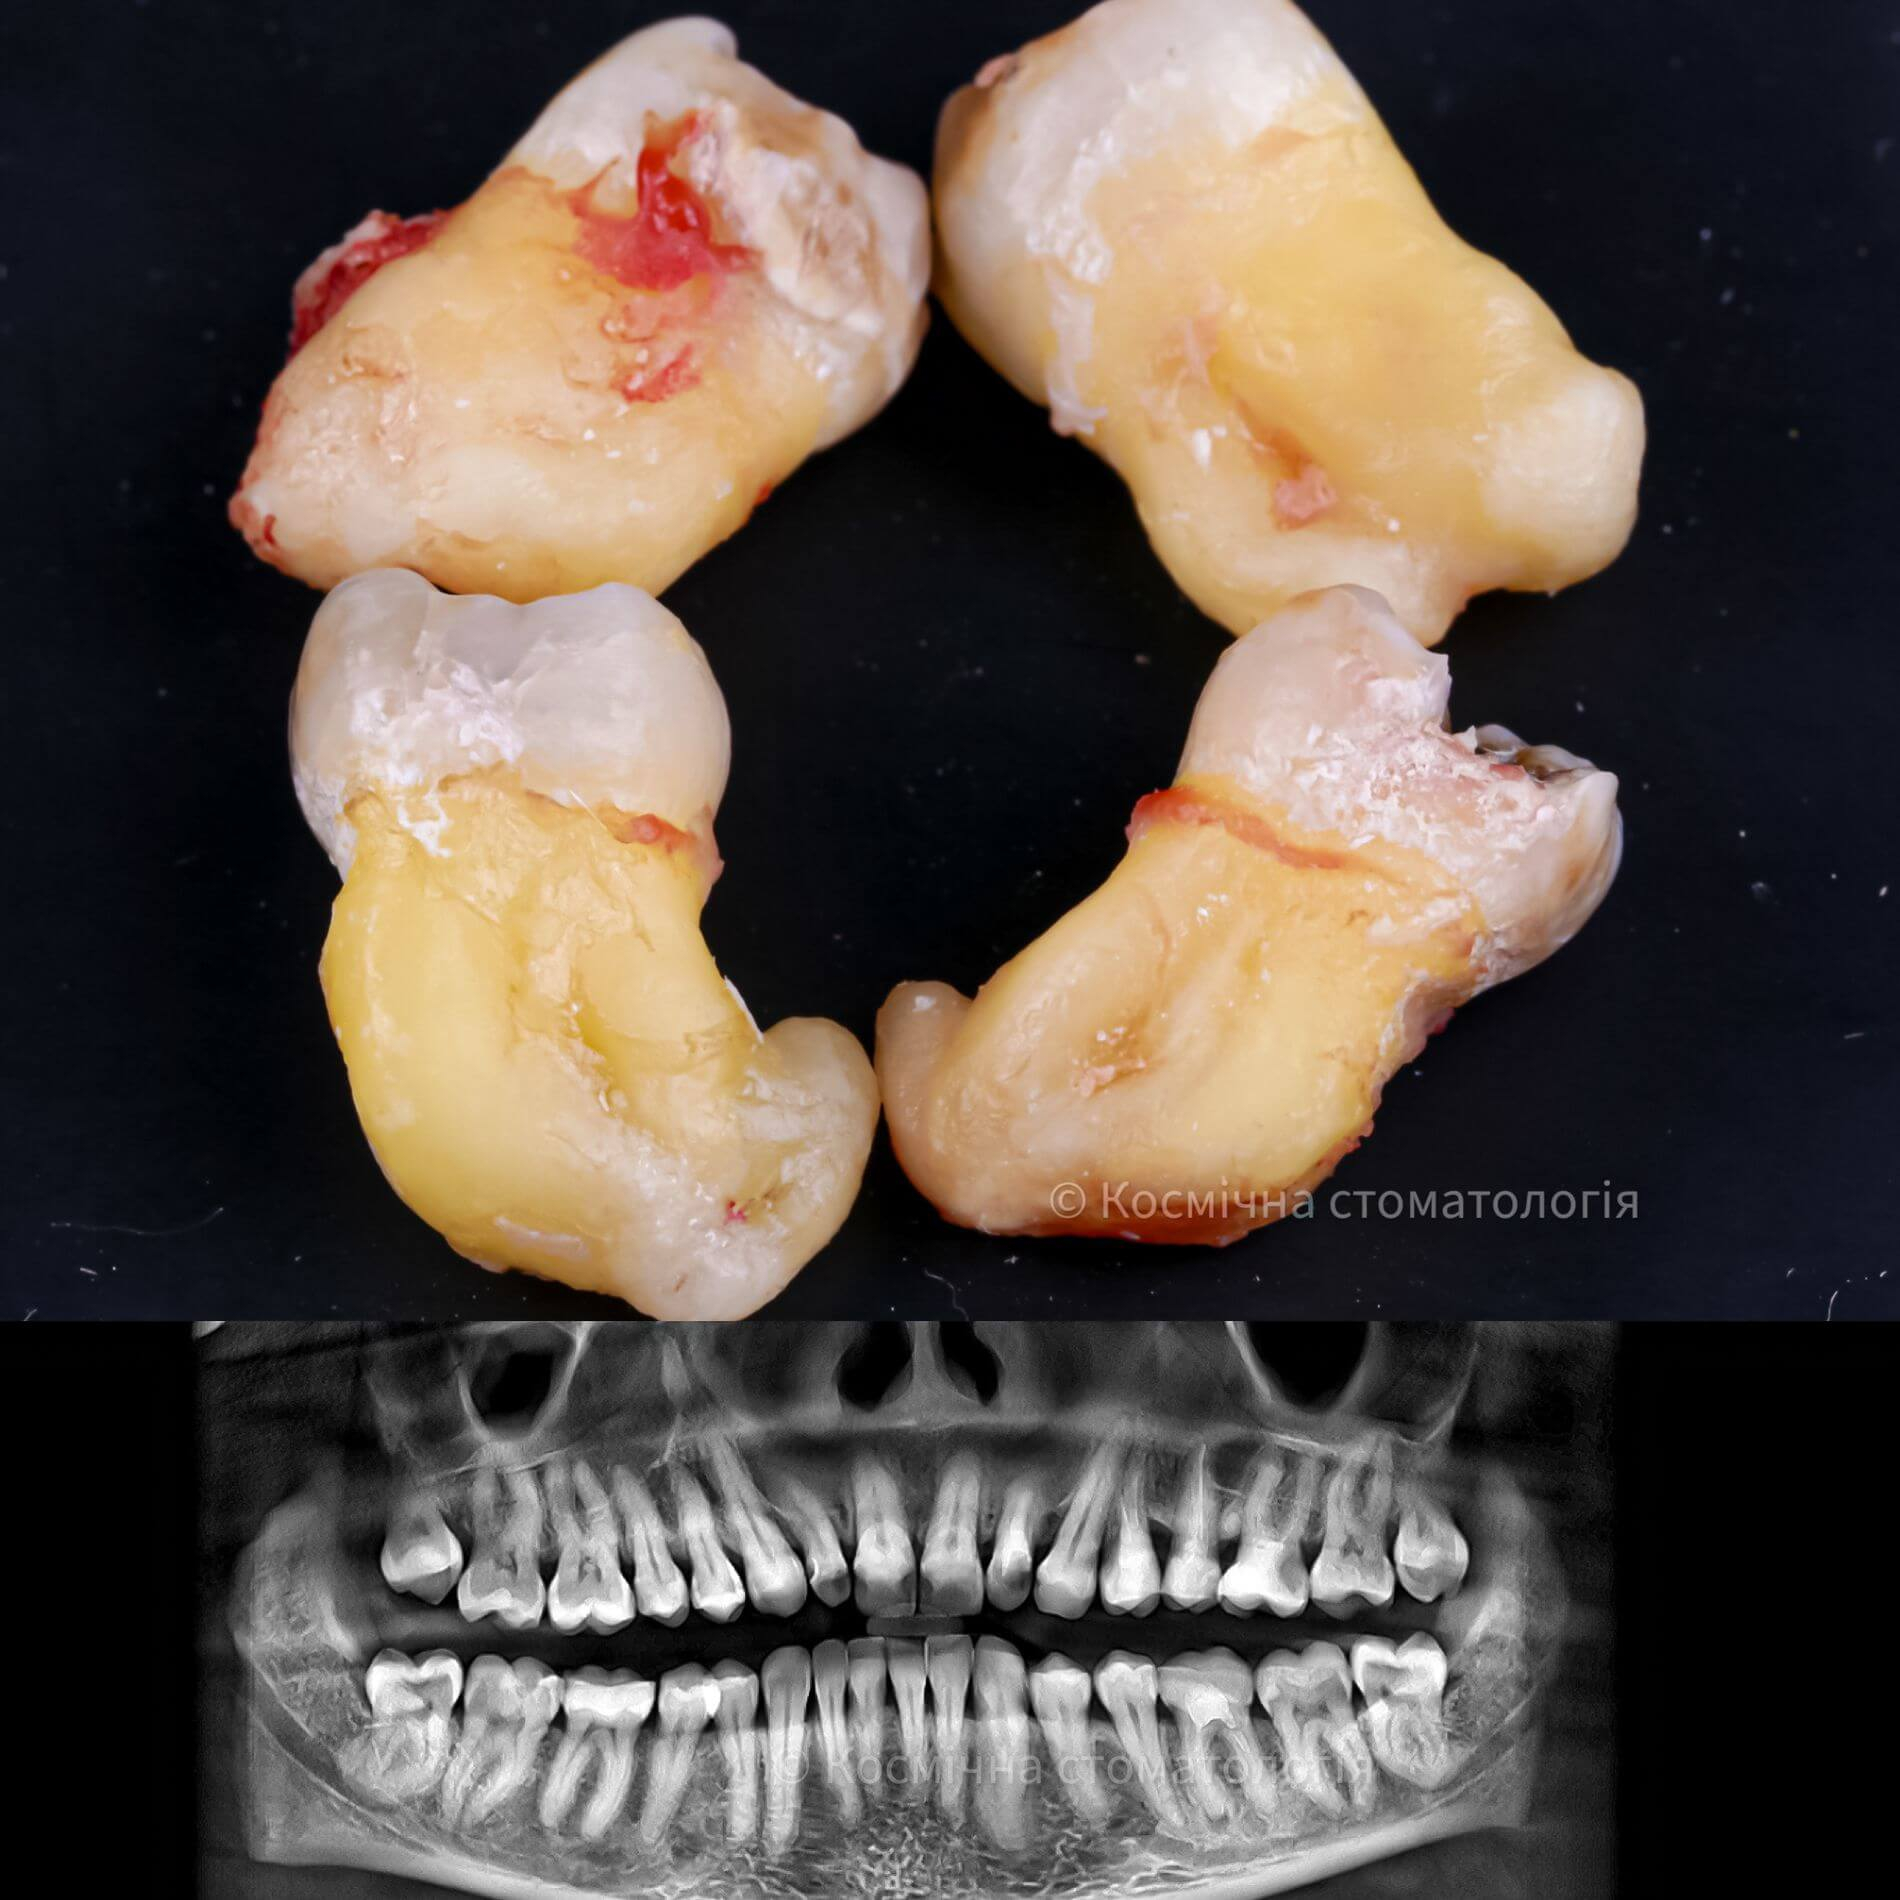

Види видалення зубів мудрості

- Повне видалення зуба - якщо зуб повністю прорізався та має зрощені корені.

- Окреме видалення коронки зуба та його коренів - якщо зуб прорізаний і корені ростуть по окремо.

- Видалення зуба за схемою 1 або 2 із розрізом ясна - якщо зуб прорізаний частково.

- Розріз ясна, звільнення зуба від прилеглої кістки ультразвуком та видалення за схемою 1 або 2 - якщо зуб не прорізався, але турбує.

Галерея